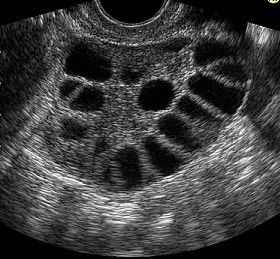

Το υπερηχογράφημα μπορεί να είναι απόλυτα φυσιολογικό ή να εντοπίσει καλοήθη προβλήματα στις ωοθήκες (κύστη ωοθήκης, πολυκυστικές ωοθήκες κ.λπ.) ή στη μήτρα (ενδομητρικός πολύποδας, ινομυώματα κ.λπ.), συγγενείς ανωμαλίες της μήτρας (διάφραγμα μήτρας, δίκερως, δίδελφυς μήτρα κ.α.) και σπανιότερα νεοπλασίες του γεννητικού συστήματος.

Η τρισδιάστατη τεχνολογία μας βοηθά να απεικονίσουμε καλύτερα πιθανές συγγενείς ανωμαλίες της μήτρας και άλλα προβλήματα όπως κύστεις ωοθηκών, ενδομητρικούς πολύποδες και ινομυώματα, να τα εντοπίσουμε καλύτερα στο χώρο και να ελέγξουμε την αγγείωσή τους.